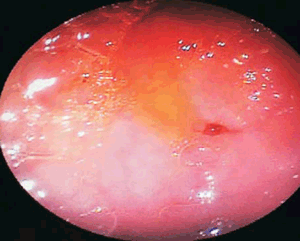

La endoscopía digestiva confirma a nivel distal presencia de un fondo de saco con una mínima perforación de aproximadamente 1 mm de diámetro (membrana duodenal perforada) (Figura 6). Se coloca balón logrando dilatación sin pasaje total de endoscopio.

Figura 6: Imagen de la endoscopía digestiva de la paciente; se observa membrana duodenal fenestrada.